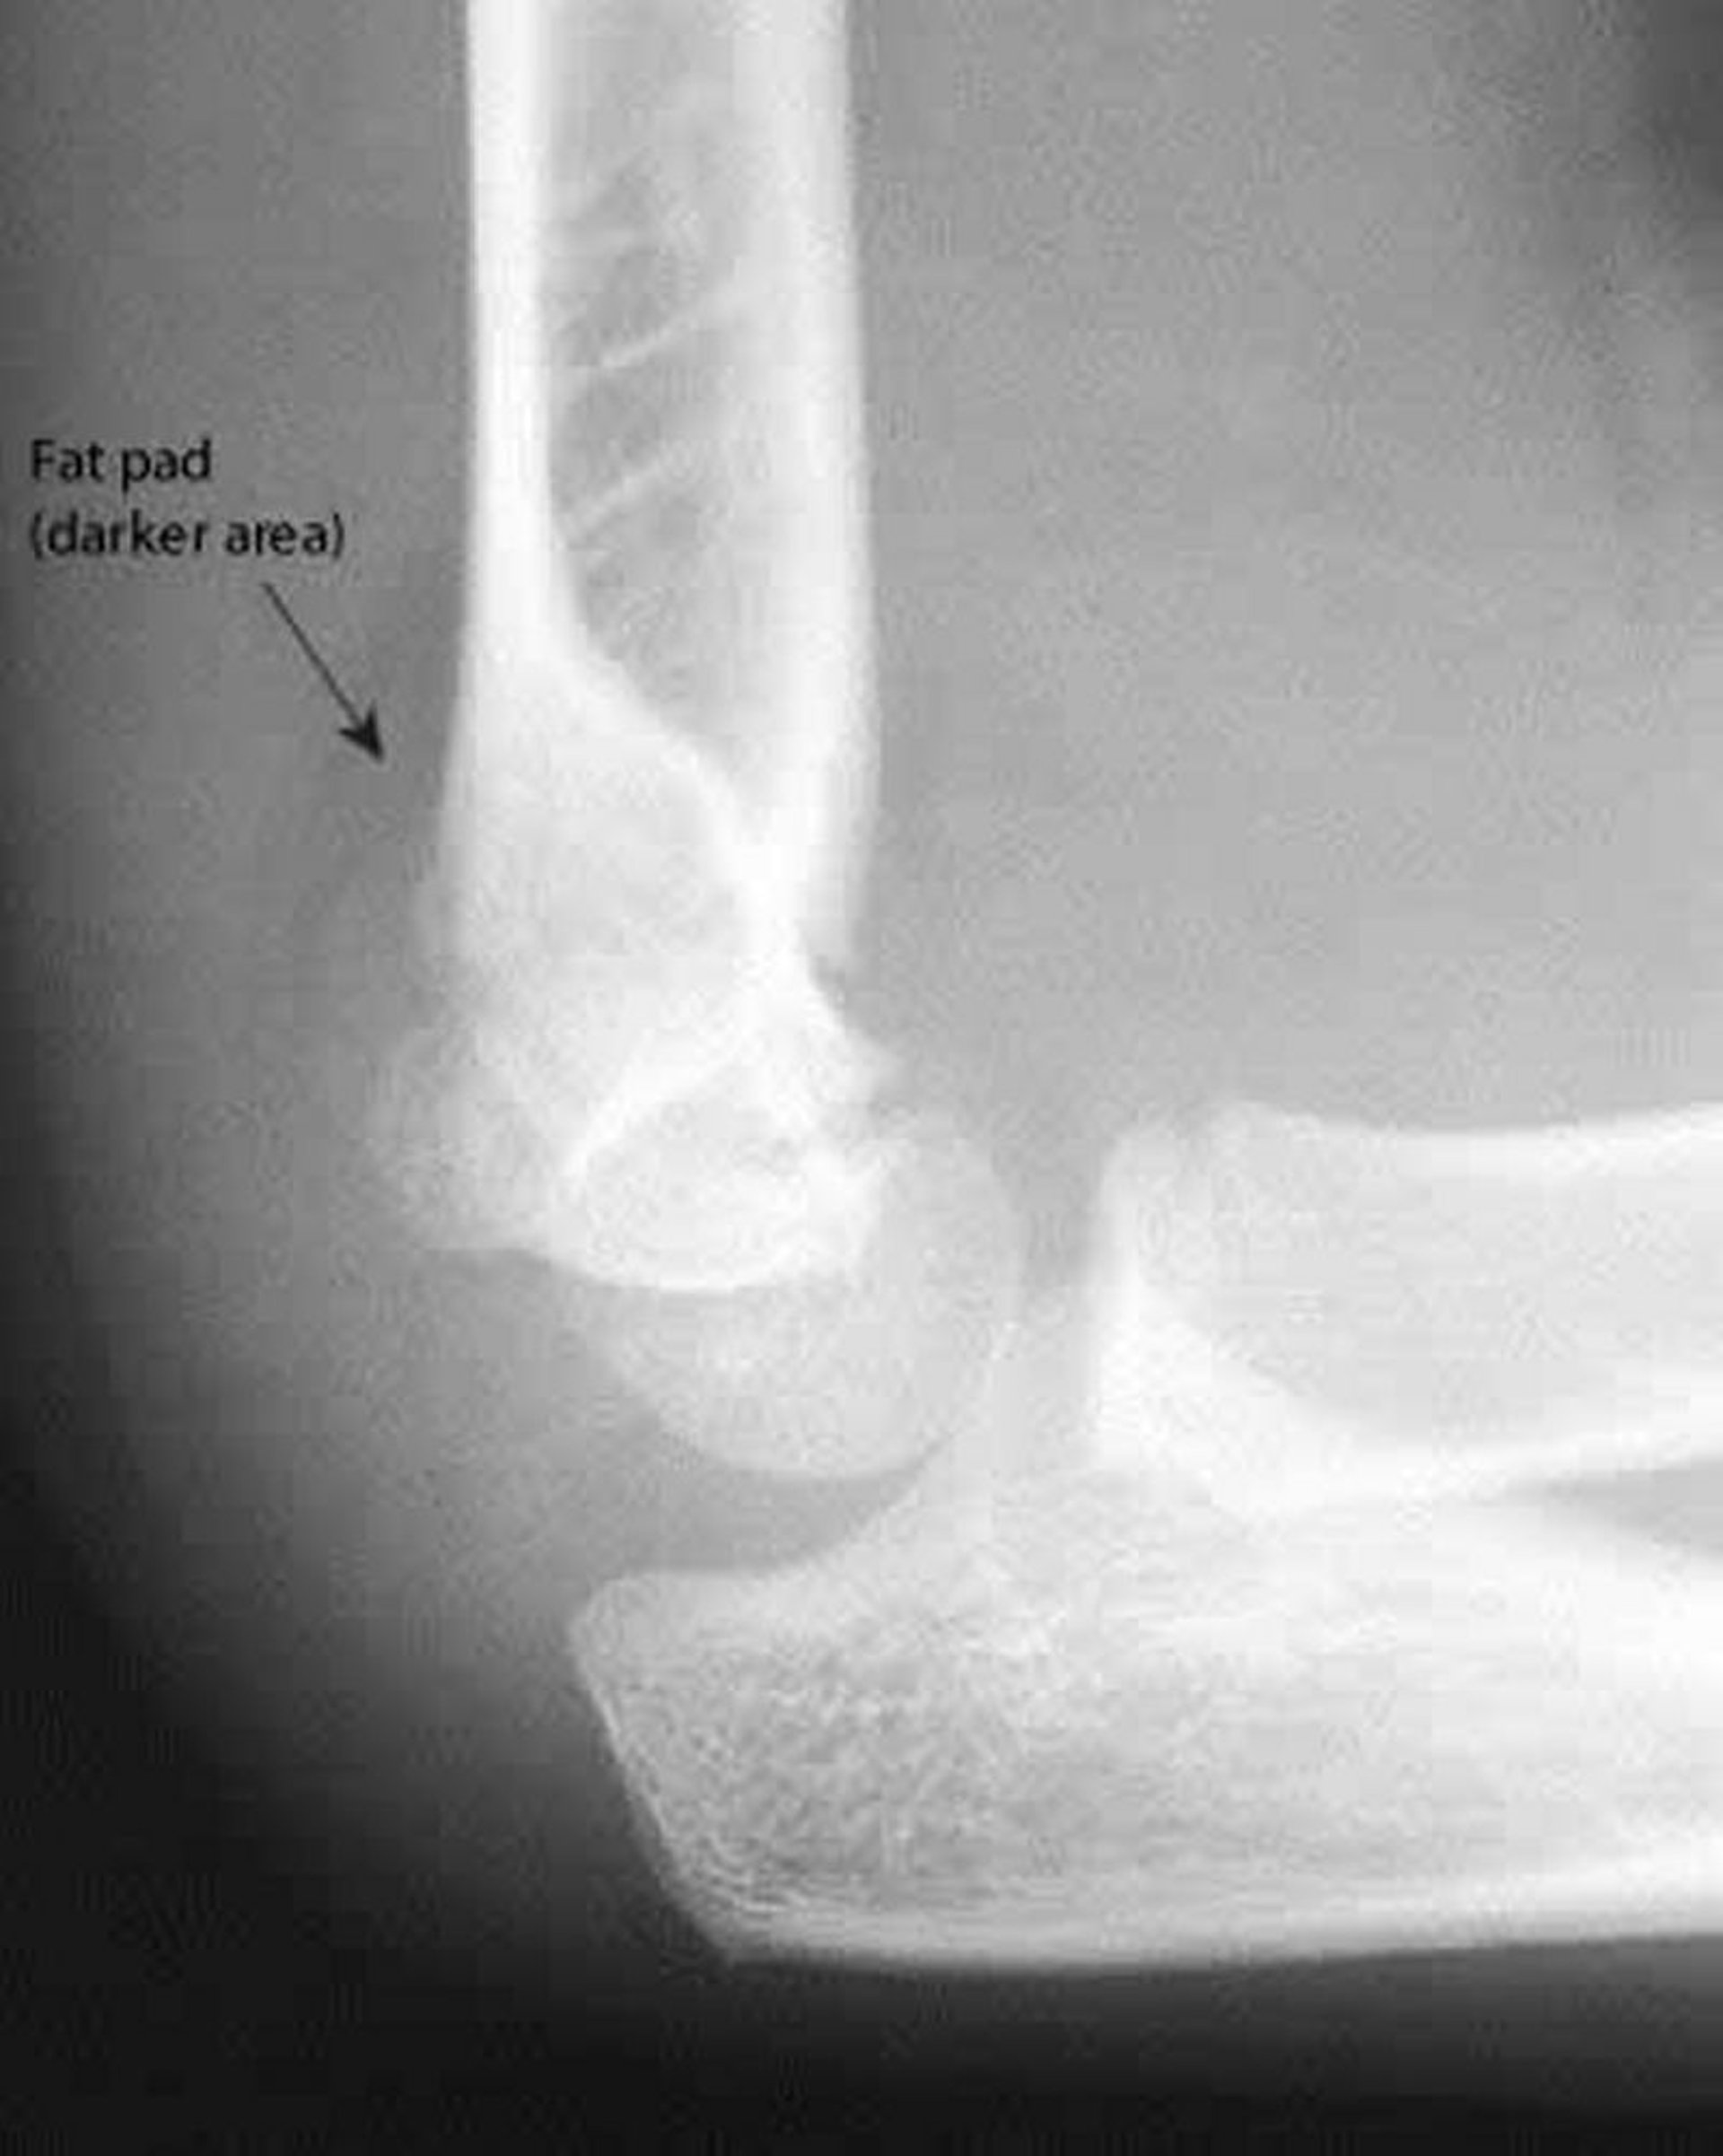

Задня жирова подушка

Задня жирова подушка завжди свідчить про наявність патології. Також на даній рентгенограмі передня плечова лінія не перетинає посередині голівку плечової кістки.

Знімок люб'язно надано лікарем Даніелем Кампаньє [Danielle Campagne], MD.